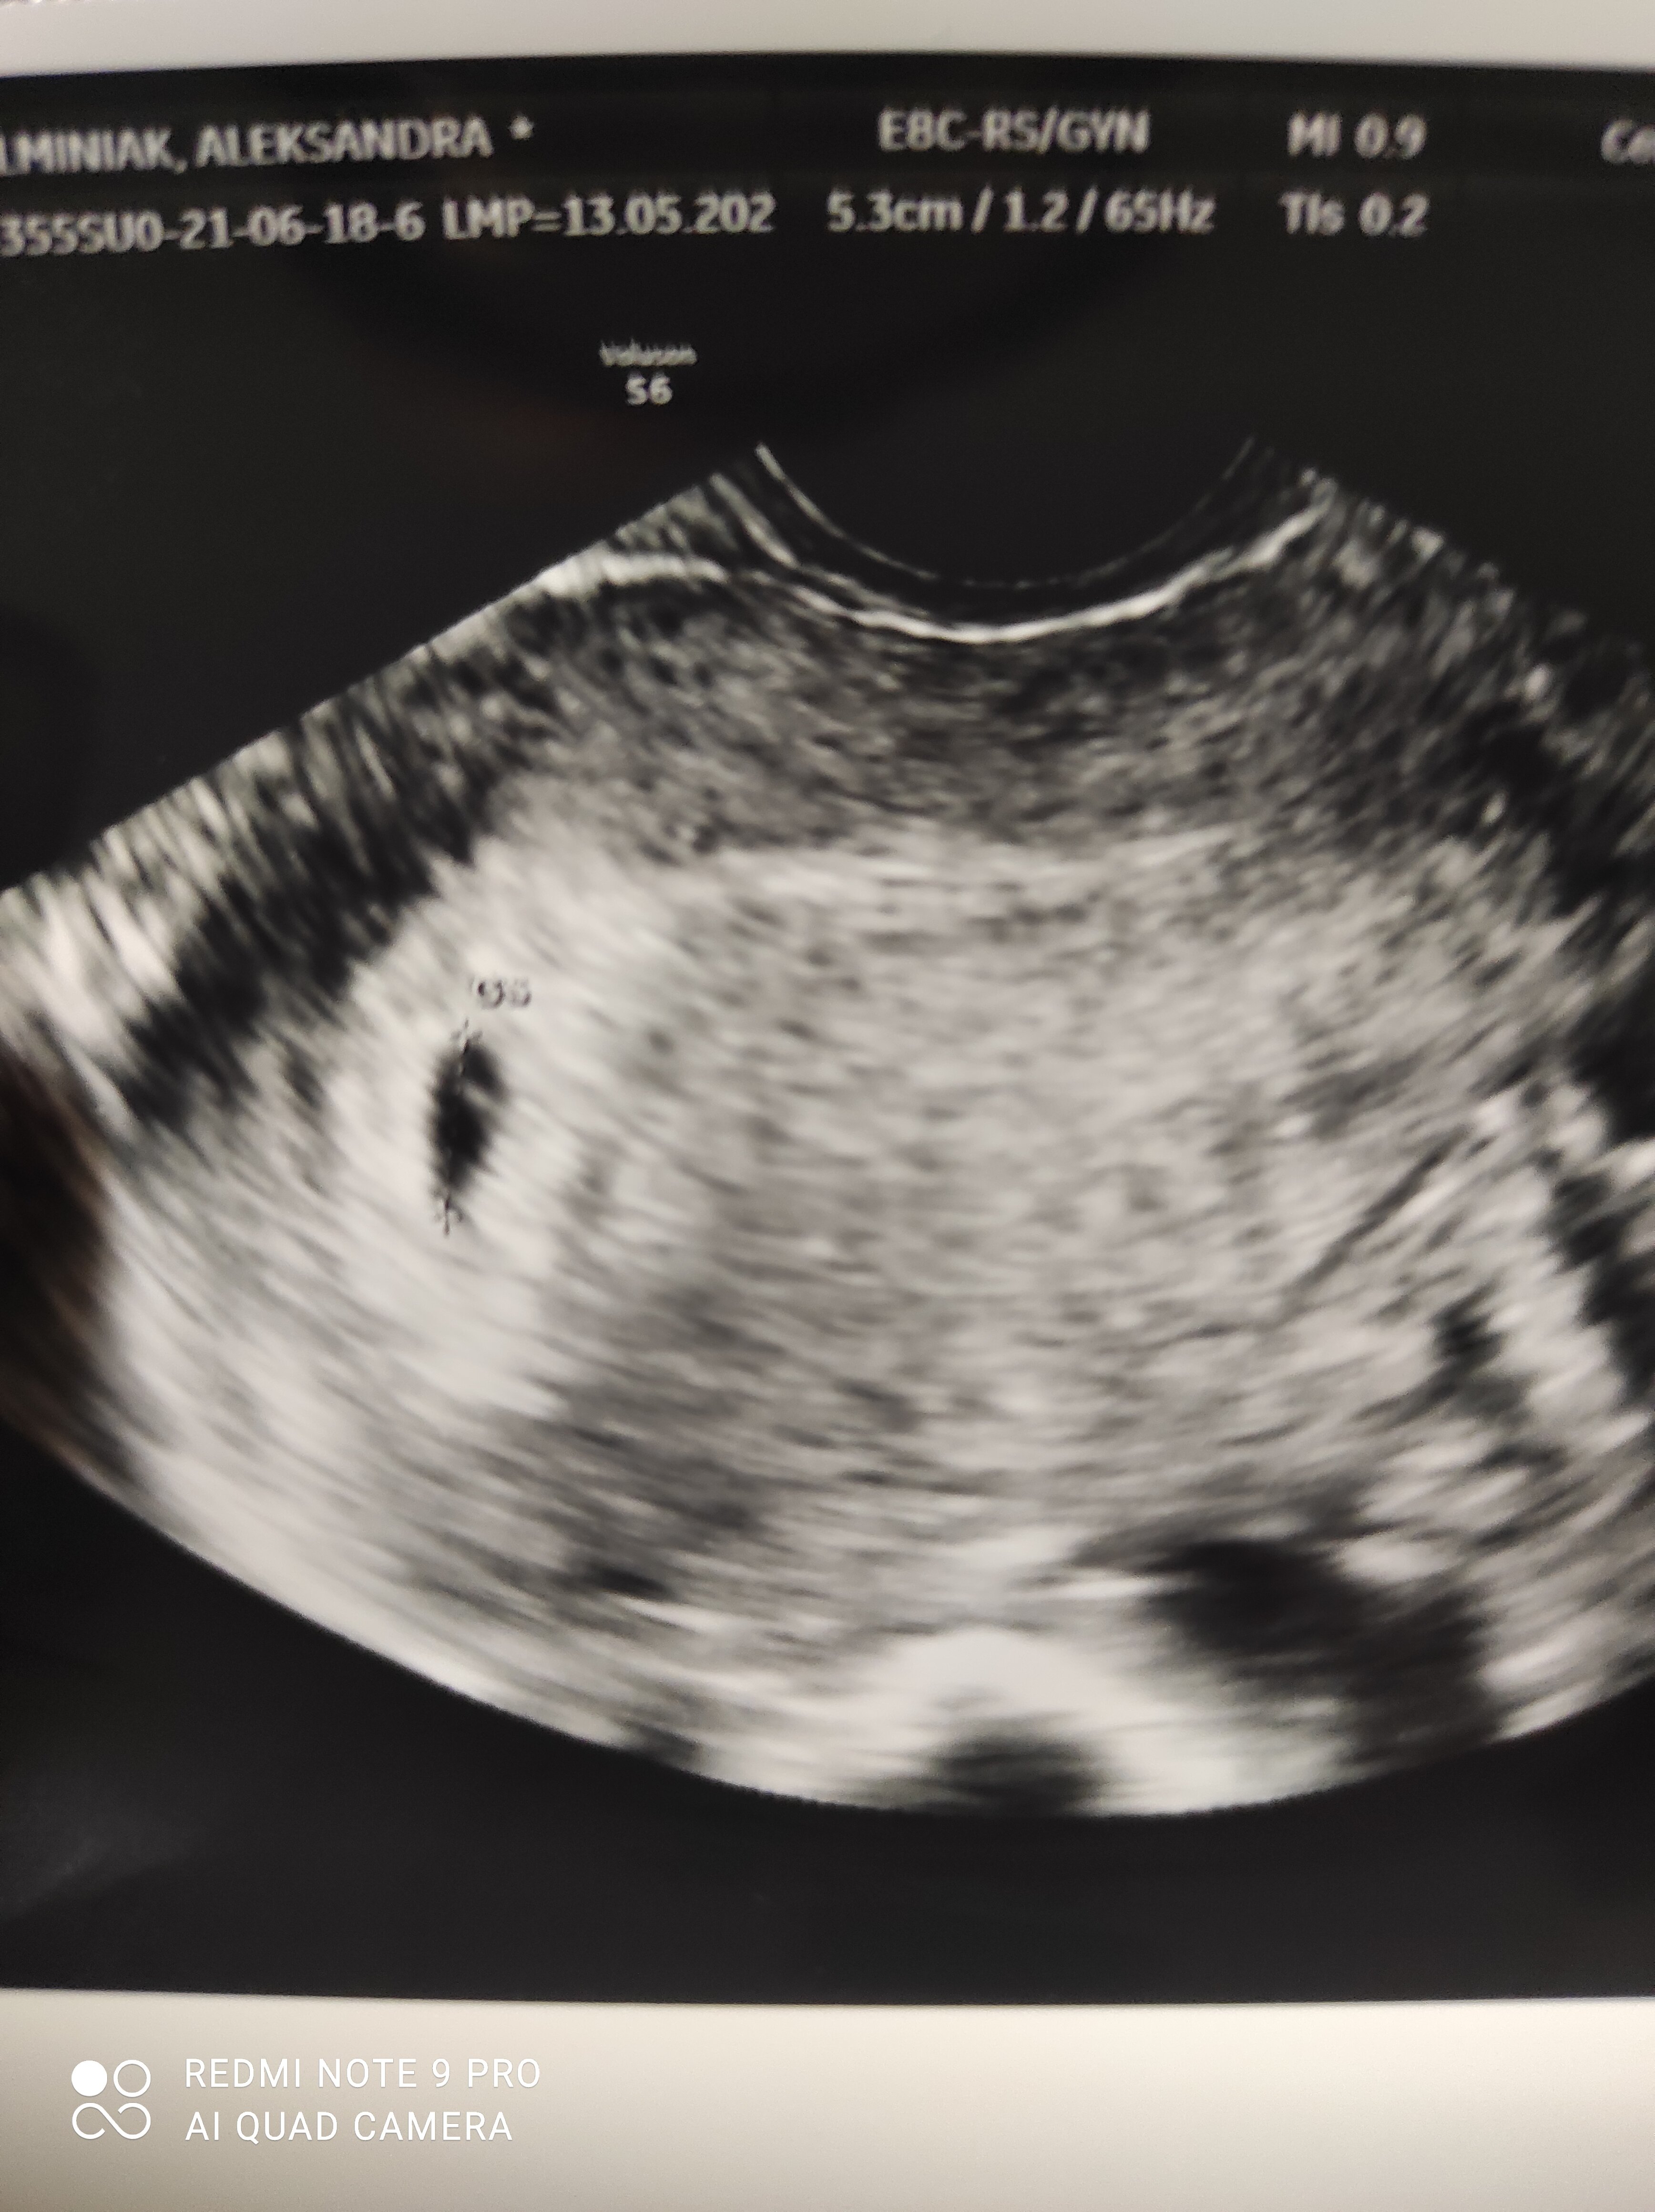

Poznajcie mojego małego fistaszka. Niestety trafiłam na jakiegoś marnego lekarza (mimo że prywatny) który stwierdził że nie da się określić daty porodu ani po zarodku bo jest za malutki ani po pęcherzyku chociaż pęcherzyk nie jest mały nie wiem zdziwiło mnie to ale powiedział że skoro mieliśmy monitoring to data porodu powinna być około 17 lutego. Cóż nie jestem może usatysfakcjonowana do końca ale cieszę się że go zobaczyłam ☺️☺️❤️❤️❤️ Teraz tylko spokojnie czekać do 5.07 i już na bank będzie serduszko. 😁.

Oo. To tak to może wyglądać na moim etapie 😍